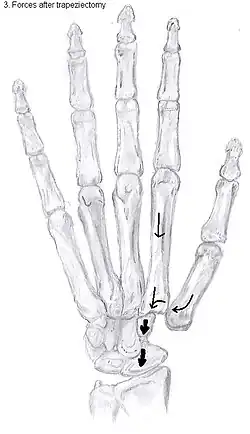

Trapeziectomy

During trapeziectomy,[30] the trapezium bone is removed without any further surgical adjustments. The trapezium bone is removed through an approximately three centimeter long incision along the lateral side of the thumb. To preserve surrounding structures, the trapezium bone is removed "by splitting" it into pieces.

An empty gap is left by the trapeziectomy and the wound is closed with sutures. Despite this gap, no significant changes in function of the thumb are reported.[27] After the surgery, the thumb will be immobilized with a cast.

Trapeziectomy with tendon interposition

Some physicians still believe that it is better to fill the gap left by the trapeziectomy. They assume that filling the gap with a part of a tendon is preferable in terms of function, stability and position of the thumb. This is based on the assumption that interposition can help maintain the space between the metacarpal and the scaphoid, which will improve comfort and capability. Neither of these assumptions is supported by experimental evidence.

Trapeziectomy with ligament reconstruction

Another technique is used to reconstruct the volar beak ligament after trapeziectomy. The rationale is that ligament reconstruction(LR) helps maintain the gap between the metacarpal and the scaphoid, and that a larger gap is associated with greater comfort and capability.[32] Again these possibilities are not supported by experimental evidence.

During this procedure the anterior oblique ligament is reconstructed using the FCR tendon. There is a wide variety in techniques to perform this LR, but they all have a similar goal.

Trapeziectomy with LRTI

Some physicians believe that combining LR with TI will help maintain gap between the metacarpal and the scaphoid.[33] And that doing so will improve comfort and capability. Keep in mind that these aspects of the rationale are not supported by experimental evidence. The evidence suggests that all of these procedures have comparable long-term results.